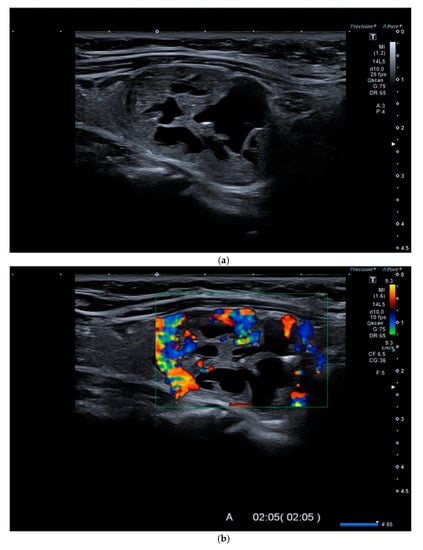

Figure 2.

(a). At B-mode Ultrasound (US), an oval-shaped nodule with mixed ecostructure, some internal fluid areas and smooth margins, was identified (EU-TIRADS 3). (b). At color–Doppler US evaluation, the lesion appeared with internal and peripheral vascularization (pattern III). (c). At Strain Ratio Elastography (SRE) evaluation, the lesion appeared soft (SR 1.13). (d). At Shear Wave Elastography (SWE) evaluation, the lesion appeared soft (2.24 m/s). (e). At CEUS evaluation, the lesion appeared solid and richly vascularized, similar to the surrounding thyroid parenchyma without wash-out. At histology, the lesion was confirmed to be a follicular hyperplasia.